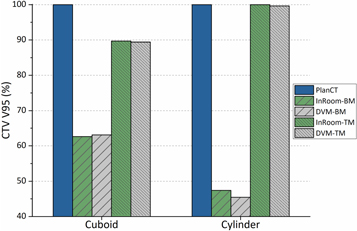

The CTV coverage (V95%) and dose distributions in both scenarios are illustrated in figures 4 and 5. The CTV coverage (V95%) differences between InRoom-BM and DVM-BM and between the InRoom-TM and the DVM-TM, were minor in both scenarios (0.46% and −0.28% for scenario 1, −1.95% and −0.38% for scenario 2, respectively; figure 4). The dose distributions of the DVM-BMs (figures 5(c) and (h)) were similar to those of the InRoom-BMs (figures 5(b) and (g)), as were the DVM-TMs (figures 5(e) and (j)) and the InRoom-TMs (figures 5(d) and (i)). With different isocenters, the dose coverage of the DVM CT changed consistently with those of the in-room CT, indicating that estimating daily dose distribution from two radiographs was feasible.

Figure 4. CTV coverage (V95%) comparisons for each scenario in phantom simulations.

Download figure:

Standard image High-resolution imageFigure 5. Isodose lines for each scenario ((a)–(e) for cuboid, (f)–(j) for cylindrical insertions) in phantom simulations. (a) and (f) are isodose lines of PlanCT, (b) and (g) are InRoom-BM, (c) and (h) are DVM-BM, (d) and (i) are InRoom-TM, and (e) and (j) are DVM-TM.